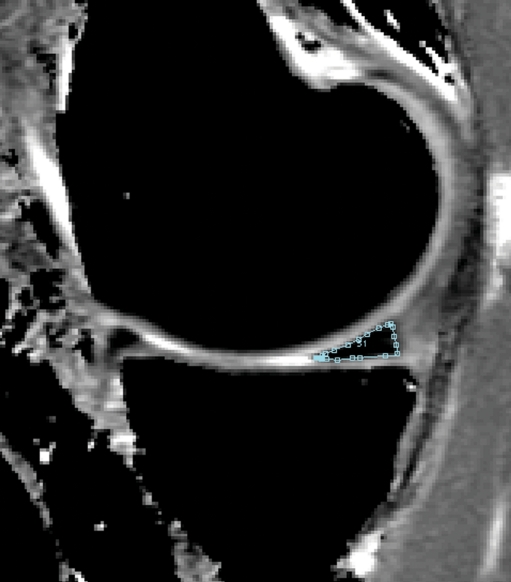

Fig. 1.

T1rho map shows the segmented posterior horn of the medial meniscus

Meniscal T1rho and T2 measurements

Images were transferred to a remote SUN/SPARC workstation (Sun Microsystems, Mountain View, CA, USA). T2 and T1rho maps were created. Meniscus segmentation was performed by using in-house software developed with an Interactive Display Language (IDL; Research Systems, Boulder, CO, USA) environment. An IDL routine was used to simplify the drawing of splines delineating meniscal areas (Fig. 1). Tissue contrast was excellent and also fluid was well shown on the sagittal T2 and T1rho maps, thus allowing meniscal segmentation in these images. In each medial and lateral meniscus, distinct regions were defined and segmentation was performed in the individual T2 and T1rho maps separately. Six different compartments of the meniscus were segmented (medial anterior, medial body, medial posterior, lateral anterior, lateral body, lateral posterior). The meniscal body was defined mesially as the first section where the anterior and posterior parts of the meniscus were connected and peripherally as the last section showing the meniscus without partial volume effects, which were characterized by a change in the signal intensity of the meniscus compared with the signal intensity of the adjacent sections. The posterior border of the posterior horn of the lateral meniscus was defined by the hiatus popliteus. The fascicles were not included in the analysis. The mesial and peripheral borders separating the meniscus from the roots and capsular ligaments were identified on the basis of partial volume effects and signal intensity changes: only those areas that had the same signal intensity as the more central aspects of the menisci were segmented. After segmentation, an IDL routine was used to calculate the mean T2 and T1rho values from the regions of interest created on the maps.